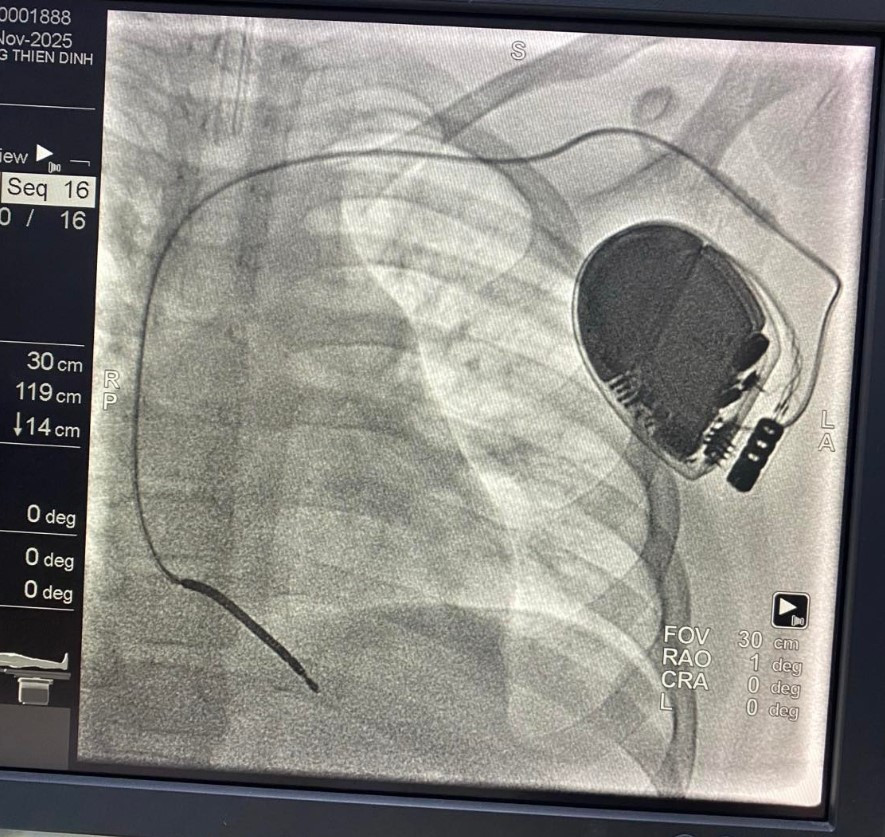

ngung-tim.jpg

Thực hiện cấy máy khử rung tim tự động cho trẻ - Ảnh BVCC

Tại Bệnh viện Nhi Đồng Thành Phố, Trung tâm Tim mạch đã quyết định cấy máy khử rung tim tự động (ICD) cho bé – một thiết bị có khả năng phát hiện và sốc điện ngay lập tức khi xuất hiện cơn nhịp nhanh thất nguy hiểm, ngăn chặn đột tử.

Đây là ca đầu tiên được triển khai tại bệnh viện, cũng là lần đầu ê-kíp thực hiện kỹ thuật tạo đường mổ dưới nách để cấy máy – phối hợp cùng đồng nghiệp phẫu thuật nhằm đảm bảo tính thẩm mỹ tối ưu, tránh để lại sẹo trước ngực như cách làm truyền thống.